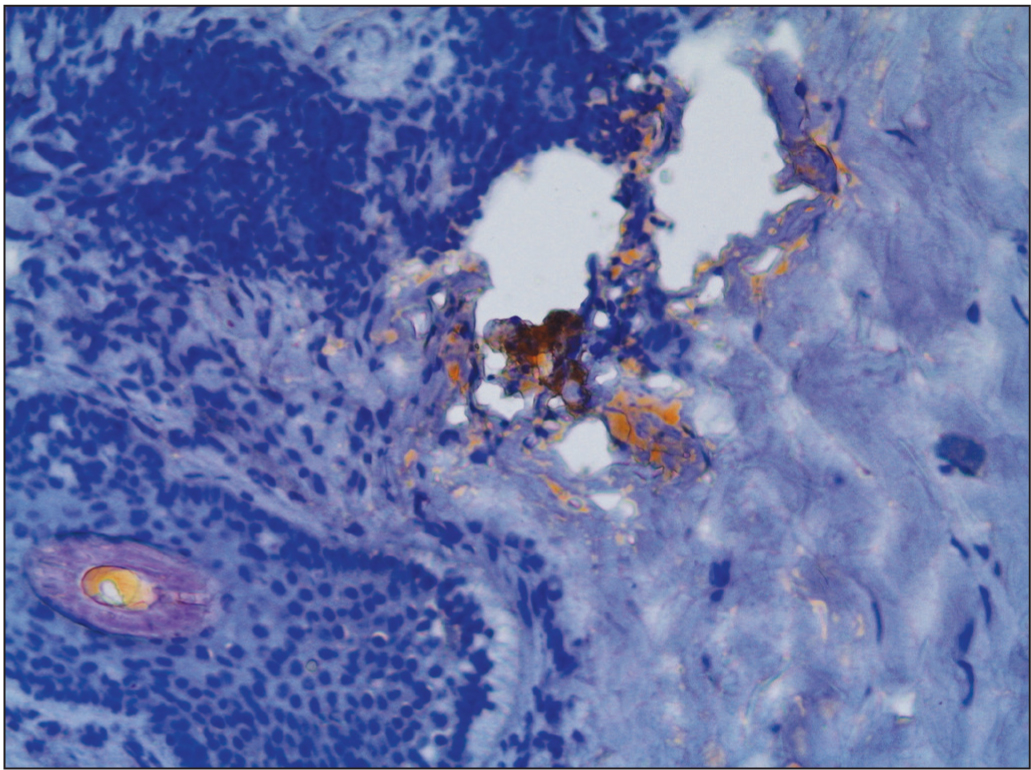

Гистологически основная область некробиоза коллагена располагается в нижних отделах дермы; вокруг нее наблюдается инфильтрат, состоящий из фибробластов, лимфоидных клеток и гистиоцитов (рис. 3). При окраске Суданом III обнаруживается характерное внеклеточное отложение липидов (рис. 4), а при окраске толуидиновым синим возможно выявление муцина [24].

Рис. 3. Гистологический препарат. Лимфогистиоцитарный инфильтрат вокруг области некробиоза коллагена.

Рис. 4. Гистологический препарат. Внеклеточное отложение липидов.